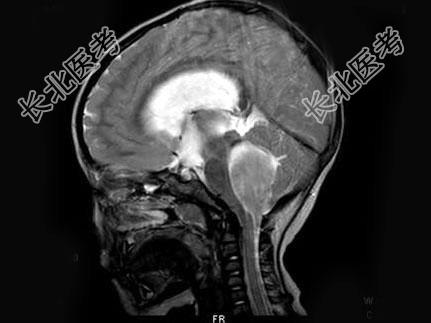

- 单项选择题女,3岁, 头痛4个月,MRI平扫及增强扫描, 最可能的诊断为 ( )

A、第四脑室脑膜瘤

B、第四脑室室管膜瘤

C、第四脑室乳头状瘤

D、第四脑室星形细胞瘤